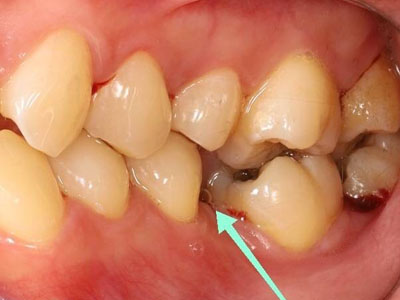

ภาพแสดงฟันล้มเข้าหาช่องว่างจากการสูญเสียฟันกรามและเกิดช่องห่างในฟันซี่ข้างเคียง

ภาพแสดงฟันล้มเอียงเนื่องจากการสูญเสียฟันกรามไปนาน

เมื่อสูญเสียฟันซี่ใดซี่หนึ่ง จะเป็นฟันกรามใหญ่ ฟันกรามน้อย หรือฟันหน้าก็ตาม ฟันที่อยู่ด้านข้างจะล้มเอียงเข้าหาช่องว่าง ทำให้เกิดฟันห่างในตำแหน่งใกล้เคียง ในขณะที่ฟันคู่สบด้านบนอาจยื่นยาวเข้าหาช่องว่าง ทำให้การสบฟันเปลี่ยนแปลงไป มีจุดสะดุดขณะบดเคี้ยวอาหาร และในระยะยาวฟันที่ล้มเอียงมักจะทำความสะอาดยาก ทำให้มีปัญหาฟันผุและโรคเหงือกอักเสบตามมาได้